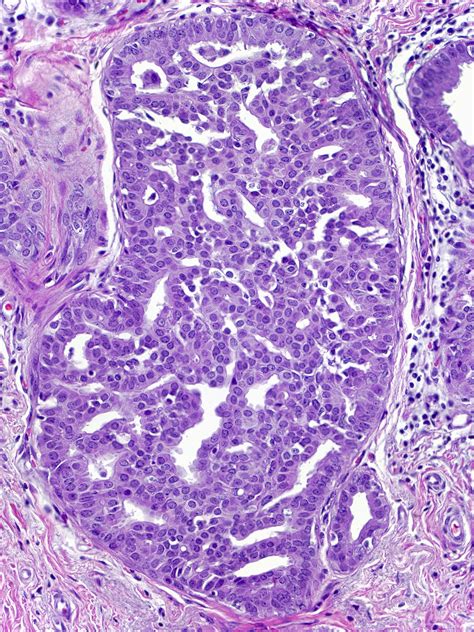

To understand Atypical Ductal Hyperplasia, it helps to look at how breast tissue changes. In a healthy breast, cells line the ducts (the tubes that carry milk). Sometimes, these cells begin to grow in an uncontrolled or disorganized manner. This process is called hyperplasia.

When those cells not only multiply but also begin to look and behave differently than normal cells—yet are not considered cancer—it is classified as “atypical.” Therefore, ADH represents a state of overgrowth where the cells lining the breast ducts have acquired some features of cancer but remain confined within the ductal structure. It is essentially a marker that indicates your breast cells are prone to genetic changes that could lead to breast cancer in the future.

During an excisional biopsy, the surgeon removes the entire area of concern along with a margin of healthy tissue. This allows the pathologist to examine the entire lesion to confirm the diagnosis and ensure no invasive cancer is hidden nearby.